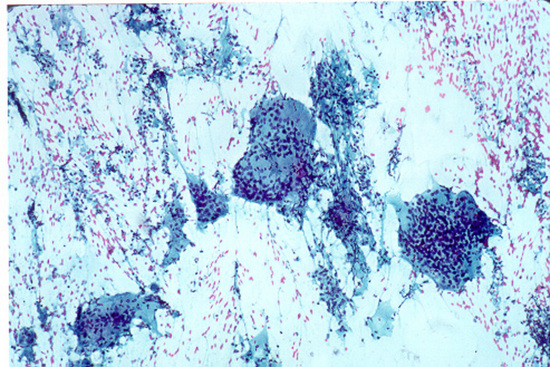

एफएनएबी चाचणी (Fine Needle Aspiration Biopsy Of The Thyroid (FNAB) Procedure)

गळ्यात गाठी आढळल्यास एफएनएबी ही चाचणी केली जाते. गाठीत सुई घालून त्यातील पेशी काढून घेतल्या जातात. या पेशींची मायक्रोस्कोपमध्ये तपासणी केल्यास थायरॉइडचं निदान केलं जातं.